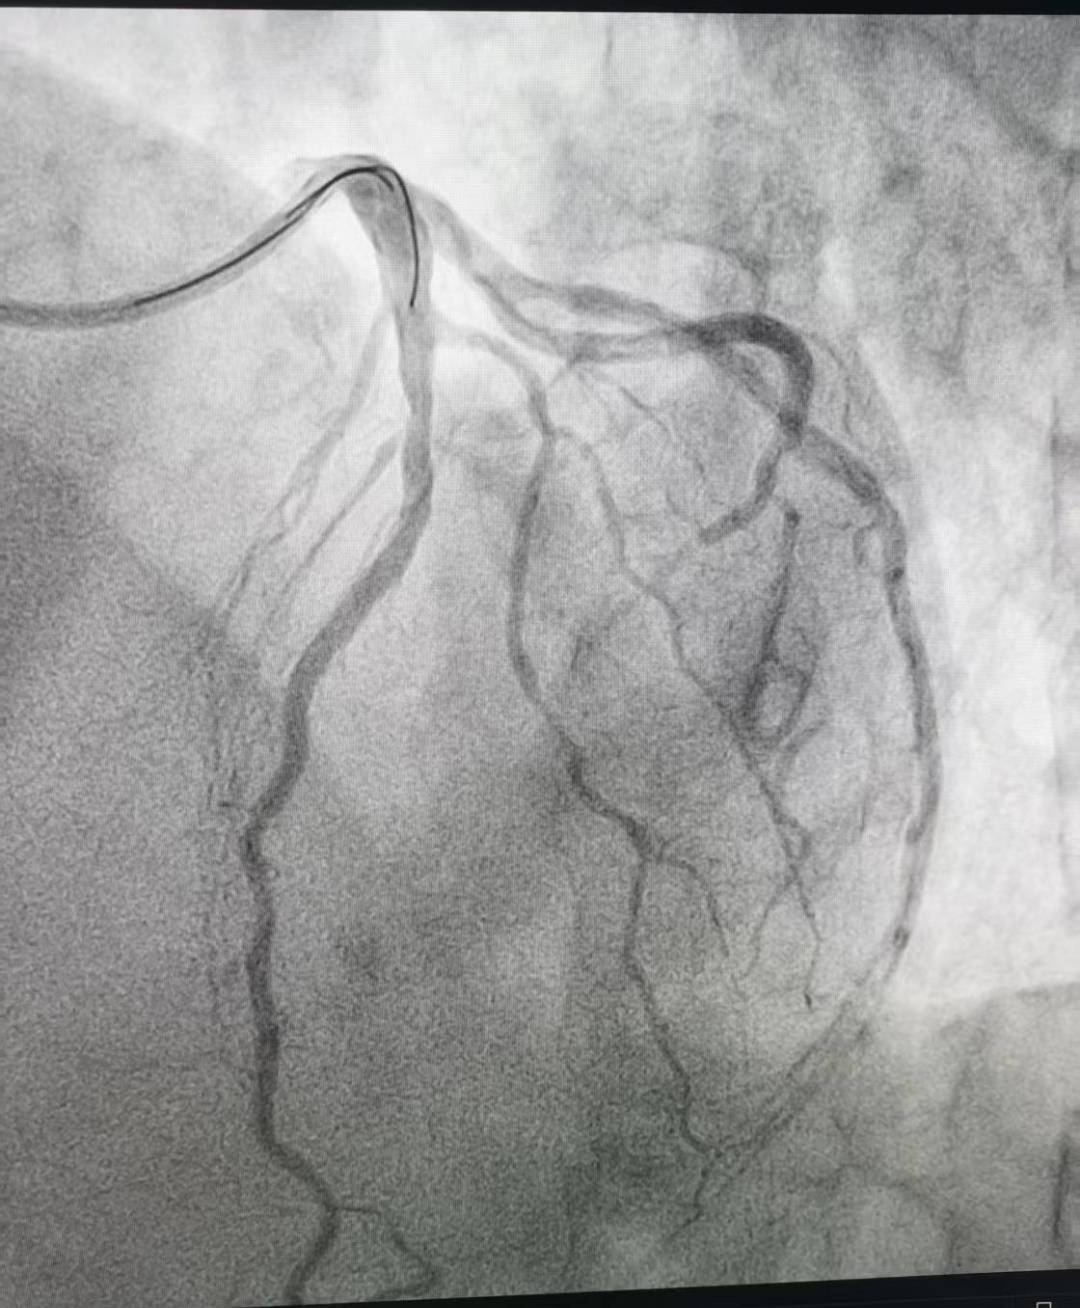

“时间就是心肌,时间就是生命!”心内三科谈金强主任和张用之主治医师立即启动急救绿色通道,为患者急诊行冠状动脉造影(CAG)以明确冠脉病情。造影结果显示:患者对角支自开口处100%闭塞!如此隐蔽的病变,不仅极度考验术者的观察力,更对冠脉解剖结构的熟悉程度提出极致挑战,稍有疏忽便可能漏诊,酿成不可挽回的结果!